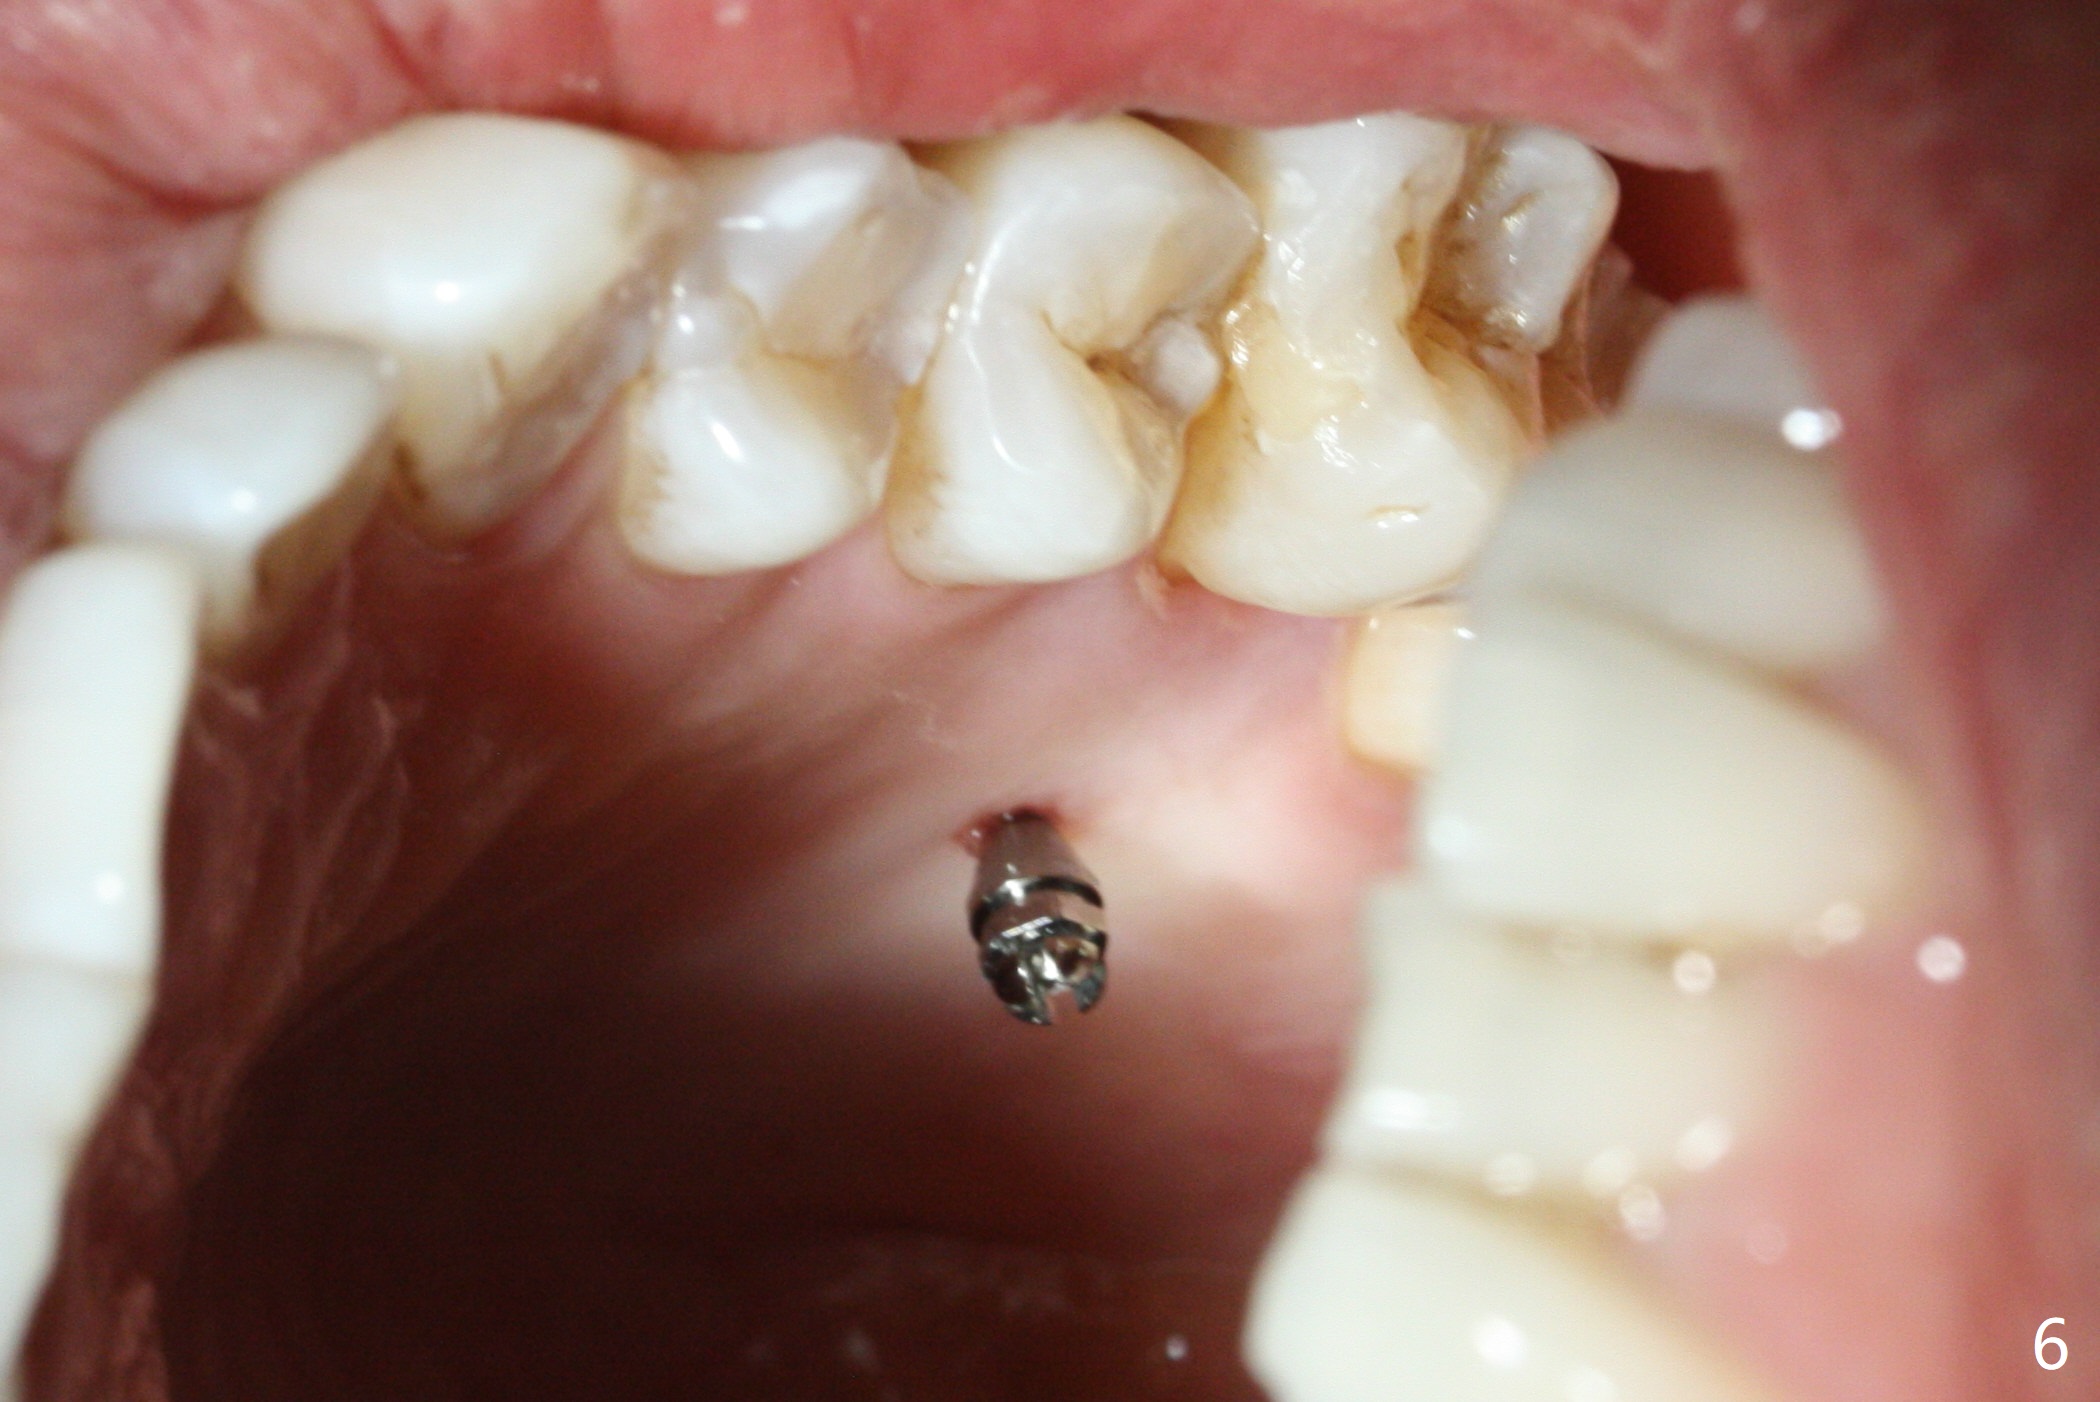

Fourteen days prior to implantation at #19 to replace a flipper (Fig.2), two minimplants are placed to intrude the supraerupted opposing tooth (#14, Fig.1). After use of minimal amount of local anesthetic (to keep proprioceptive in case root surface violation), the miniimplants are inserted ~ half of the length initially (Fig.3,4). The mesiobuccal (MB) one seems to be better positioned than the distopalatal (DP) one. When the implants are completely seated (Fig.5,6), three of PAs are taken, which suggests contact of the MB implant to the MB root of the tooth #14 (Fig.7 arrow). Immediately postop CT confirms approximation of MB and DP implants to the MB and P roots, respectively (Fig.8,9). The trajectory of these implants remain unchanged. Twelve days postop, the patient returns, uncomfortable with the palatal implant. After deep placement to bury the cuff (Fig.6) without local anesthesia (bone having no innervation), the patient feels better.